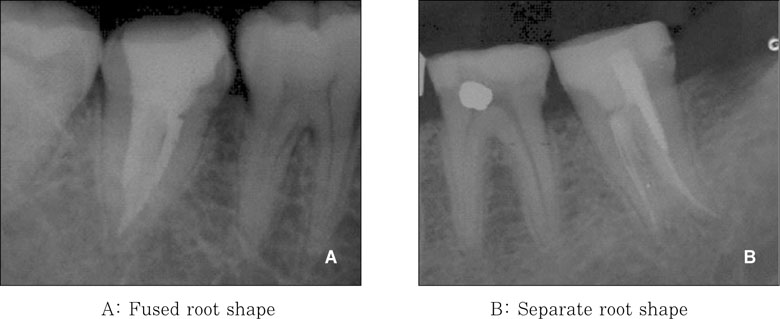

Figure 2

Classification of the C-shaped root shape.

Figure 2 Classification of the C-shaped root shape.